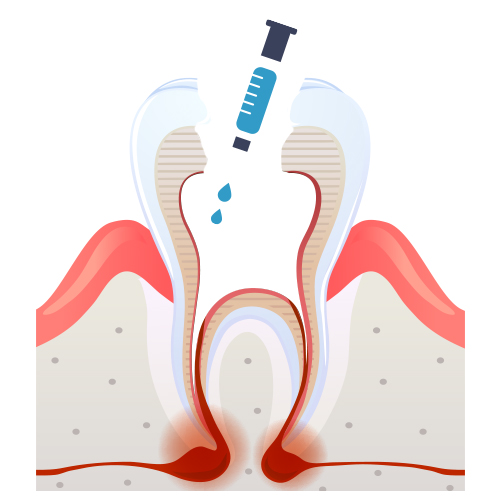

신경치료 과정

01

01

충치

02

02

충치제거

03

03

신경제거 및 길이측정

신경제거 후 소독 및 세척